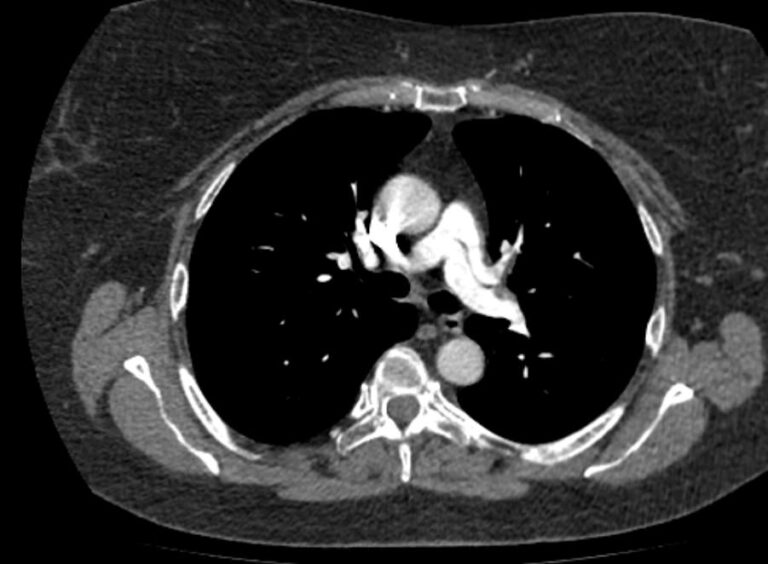

Наиболее информативным, при этом быстрым и неинвазивным (то есть без вмешательства в организм пациента), методом диагностики патологии легочной артерии является мультиспиральная компьютерная томография (КТ-ангиография). Методика основана на использовании рентгеновского излучения в сочетании с цифровой обработкой данных для получения трехмерных изображений сосудистой системы.

Для визуализации кровеносных сосудов в обязательном порядке применяется контрастное усиление. Для этого в вену пациента вводится йодсодержащий контрастный препарат, который попадая в кровоток активно поглощает рентгеновские лучи и ярко контрастирует сосудистую систему, в том числе легочной артерии, на фоне окружающих тканей. Использование контраста дает возможность визуализировать даже мелкие артерии и выявить патологию.

В наших диагностических центрах КТ-ангиография легочной артерии проводится на современных мультиспиральных компьютерных томографах экспертного уровня TOSHIBA AQUILION. Оснащение аппаратов позволяет получать детальные снимки и трехмерные изображения сосудистой системы легочной артерии, при этом применение скоростной мультисрезовой методики сканирования значительно снижает уровень лучевой нагрузки на пациента.